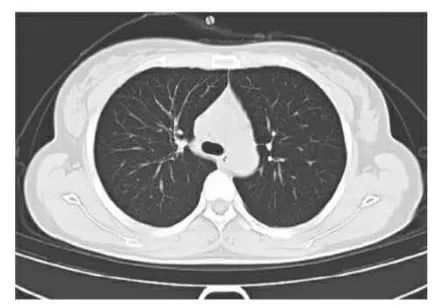

第一例患者咽试子核酸初筛阴性,影像学高度疑似,表现为双肺下叶见大片状模糊影及磨玻璃影,部分略呈扇形分布,血清学抗体证实都是阳性